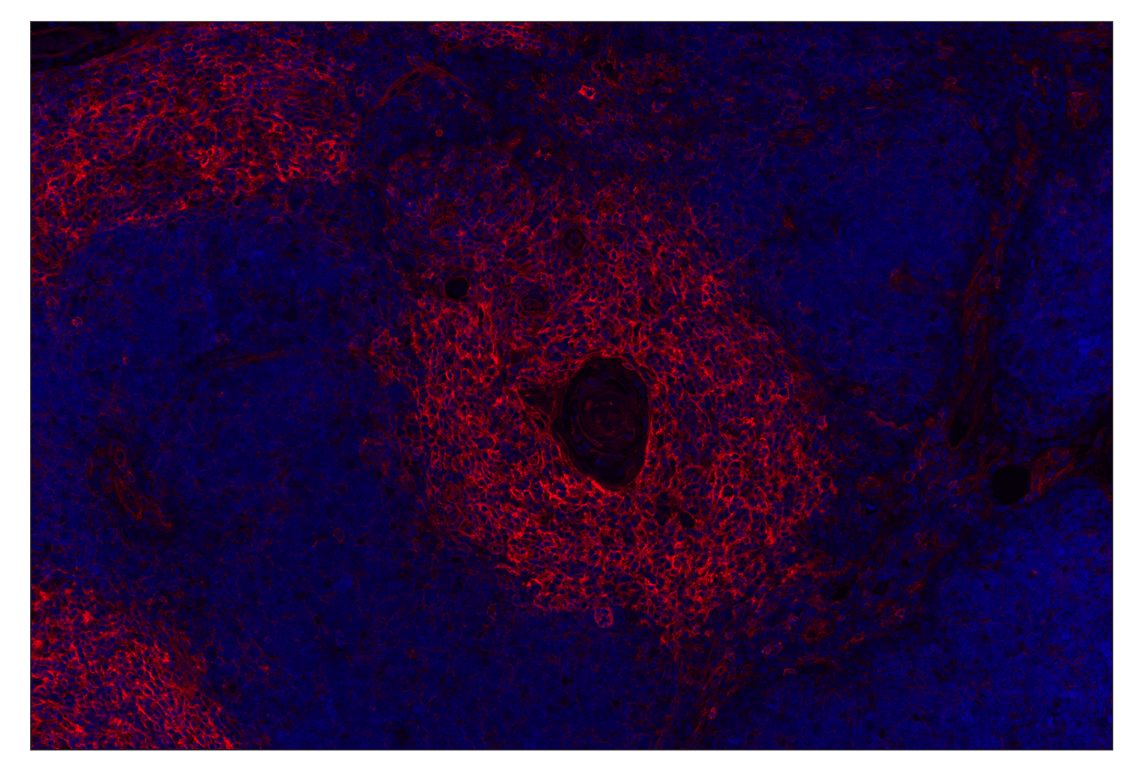

MHC Class I (EMR8-5) Mouse Monoclonal Antibody (Alexa Fluor® 555 Conjugate) #57549

MHC Class I (EMR8-5) Mouse Monoclonal Antibody (Alexa Fluor® 555 Conjugate) detects HLA-A, HLA-B, HLA-C, and HLA-E. This antibody conjugate does not cross-react with HLA-G.